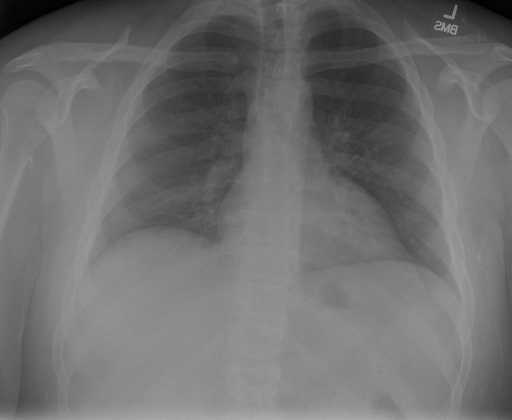

# 本文贡献 ![](./assets/images/xrayglm.png) - 借助ChatGPT以及公开的数据集,我们构造了一个`X光影像-诊断报告`对的医学多模态数据集; # 数据集 - [MIMIC-CXR](https://physionet.org/content/mimic-cxr-jpg/2.0.0/)是一个公开可用的胸部X光片数据集,包括377,110张图像和227,827个相关报告。 - [OpenI](https://openi.nlm.nih.gov/faq#collection)是一个来自印第安纳大学医院的胸部X光片数据集,包括6,459张图像和3,955个报告。 在上述工作中,报告信息都为非结构化的,不利于科学研究。为了生成合理的医学报告,我们对两个数据集进行了预处理,并最终得到了可以用于训练的**英文报告**。除此之外,为了更好的支持中文社区发展,借助ChatGPT的能力,我们将英文报告进行了中文翻译,并最终形成了可用于训练的数据集。 |数据集|数量|下载链接| |:-|:-|:-| |MIMIC-CXR-zh|-|-| |OpenI-zh|6,423|[诊疗报告](./data/Xray/openi-zh.json) 、[X光影像](https://pan.baidu.com/s/13GBsDMKf6xBZBSHpoWH_EA?pwd=k9sh)| # 快速上手 1. 安装环境 ```bash # 安装依赖 pip install -r requirements.txt # 国内换源安装依赖 pip install -i https://mirrors.aliyun.com/pypi/simple/ -r requirements.txt ``` 此时默认会安装`deepspeed`库(支持`sat`库训练),此库对于模型推理并非必要,同时部分`Windows`环境安装此库时会遇到问题。 如果想绕过`deepspeed`安装,我们可以将命令改为: ```bash # 安装依赖 pip install -i https://mirrors.aliyun.com/pypi/simple/ -r requirements_wo_ds.txt # 安装SwissArmyTransformer pip install -i https://mirrors.aliyun.com/pypi/simple/ --no-deps "SwissArmyTransformer>=0.3.6" ``` 2. 模型推理 CLI推理: ```python python cli_demo.py --from_pretrained checkpoints/finetune-XrayGLM-05-25-01-04 --prompt_zh '详细描述这张胸部X光片的诊断结果' ``` 更多[参数](https://github.com/WangRongsheng/XrayGLM/blob/main/cli_demo.py#L16) # 效果展示 诊断: |X光影像|诊疗报告(医生)|XrayGLM| |:-|:-|:-| |![](./data/Xray/2_1.png)|根据X射线图像,心脏大小正常,肺部看起来很清晰。已经排除了肺炎、积液、水肿、气胸、腺病、结节或肿块的存在。该发现表明一切正常。换句话说,总体印象是胸部正常。|X光片显示,心脏大小正常。肺部没有气胸或胸腔积液的证据。骨骼结构看起来没有任何异常。总的来说,X光片表明没有发现急性心肺疾病的迹象。| |![](./data/Xray/2882_1.png)|X光图片显示没有扭曲的区域、可疑的骨质不透明度或胸腺积液。心脏大小轻微增大,但非常稳定。此外,没有气胸的证据,肺野也正常。总体来说,X光片显示没有急性心脏异常,但要注意轻微的心脏扩大。|X光片显示,心脏大小正常。肺部和纵隔轮廓清晰,没有气胸或胸腔积液的证据。骨骼结构完整,没有任何急性异常。| |![](./data/Xray/2577_1.png)|心影形态在正常范围内。没有急性骨质异常。有可能出现没有明显的吸水或肺实质状况的线索。没有大面积积液或气胸。有可能怀疑其有误吸或肺实质问题。为了确诊和治疗,可能需要进行适当的影像学随访。|心脏大小正常,肺部和纵隔轮廓清晰。没有急性异常或活动受限的证据。没有任何明显的气胸、胸腔积液或肺不张的迹象。此外,也没有发现任何局灶性骨质异常或其他急性疾病。| 多轮对话: |X光影像|诊疗报告(医生)| |:-|:-| |![](./data/Xray/861_1.png)|右侧主动脉突出观察到。心脏大小正常。胸部未发现明显的肺气肿、胸膜积液或可疑的肺部病变。报告指出已知右侧主动脉情况正常。| ```bash >> X光影像路径:./data/Xray/861_1.png >> 用户:这是一张什么图? >> XrayGLM:这张图片显示的是一张肺部检查的X光片。 >> 用户:请描述这张胸部X光片的诊断结果 >> XrayGLM:心脏大小正常,肺部清晰。没有急性心肺疾病的证据。 >> 用户:是否存在肺气肿? >> XrayGLM:没有肺气肿。心脏大小正常,肺部清晰。没有发现急性心肺疾病的证据。 >> 用户:平时饮食该注意什么? >> XrayGLM:饮食应该健康,均衡。建议增加蛋白质的摄入量,因为蛋白质有助于维持肌肉和骨骼的健康。多食用蔬菜、水果、全谷物以及健康的脂肪来源如橄榄油、鱼类等可以帮助获得足够的维生素和矿物质。此外,避免过度饮酒或吸烟,这些习惯可能会对心脏健康产生负面影响。 ``` # 项目致谢 1. [VisualGLM-6B](https://github.com/THUDM/VisualGLM-6B)为我们提供了基础的代码参考和实现; 2. [MiniGPT-4](https://github.com/Vision-CAIR/MiniGPT-4)为我们这个项目提供了研发思路; 3. ChatGPT生成了高质量的中文版X光检查报告以支持XrayGLM训练; 4. [gpt_academic](https://github.com/binary-husky/gpt_academic)为文档翻译提供了多线程加速; 5. [MedCLIP](https://github.com/RyanWangZf/MedCLIP) 、[BLIP2](https://huggingface.co/docs/transformers/main/model_doc/blip-2) 、[XrayGPT](https://github.com/mbzuai-oryx/XrayGPT) 等工作也有重大的参考意义; ![](./assets/images/mpu.png) 这项工作由[澳门理工大学应用科学学院](https://www.mpu.edu.mo/esca/zh/index.php)硕士生[王荣胜](https://github.com/WangRongsheng) 、[段耀菲](https://github.com/IsBaSO4) 、[李俊蓉](https://github.com/lijunrong0815)完成,同时这项工作受到[檀韬](https://scholar.google.com/citations?hl=zh-CN&user=lLg3WRkAAAAJ)副教授、[彭祥佑](http://www.patrickpang.net/)老师的帮助支持。 *特别鸣谢:[USTC-PhD Yongle Luo](https://github.com/kaixindelele) 提供了有3000美金的OpenAI账号,帮助我们完成大量的X光报告翻译工作 # 免责声明 本项目相关资源仅供学术研究之用,严禁用于商业用途。使用涉及第三方代码的部分时,请严格遵循相应的开源协议。模型生成的内容受模型计算、随机性和量化精度损失等因素影响,本项目无法对其准确性作出保证。即使本项目模型输出符合医学事实,也不能被用作实际医学诊断的依据。对于模型输出的任何内容,本项目不承担任何法律责任,亦不对因使用相关资源和输出结果而可能产生的任何损失承担责任。 # 项目引用 如果你使用了本项目的模型,数据或者代码,请声明引用: ```bash @misc{wang2023XrayGLM, title={XrayGLM: The first Chinese Medical Multimodal Model that Chest Radiographs Summarization}, author={Rongsheng Wang, Yaofei Duan, Junrong Li, Patrick Pang and Tao Tan}, year={2023}, publisher = {GitHub}, journal = {GitHub repository}, howpublished = {\url{https://github.com/WangRongsheng/XrayGLM}}, } ``` # 使用许可 此存储库遵循[CC BY-NC-SA](https://creativecommons.org/licenses/by-nc-sa/4.0/) ,请参阅许可条款。